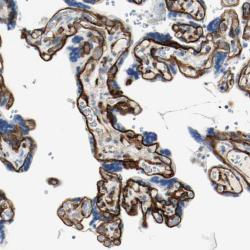

- Experimental details

- Immunohistochemical staining of human placenta shows distinct basement membrane staining.

- Validation comment

- Staining pattern partly consistent with experimental and/or bioinformatic data.